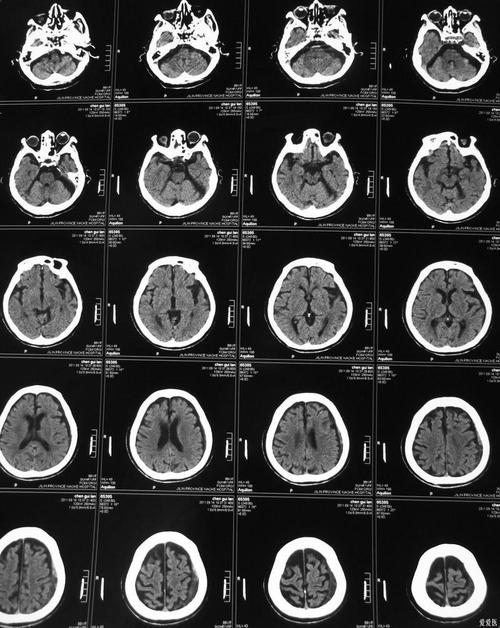

(图片来源网络,侵删)- 超早期(6小时内):在脑梗发生的极早期(尤其是前6小时内),脑组织缺血水肿尚未形成明显的密度变化,CT上可能完全显示正常,或者仅有轻微的模糊改变,极易漏诊。

- 缺血性改变出现晚:通常情况下,脑梗死后,CT上出现典型的低密度影,至少需要6-24小时,甚至更长时间,对于一些小的、非关键部位的梗死灶,CT可能数天后才能显现,或者始终显示不明显。

- 小梗死灶:对于腔隙性脑梗死(小血管堵塞引起的 small 梗死灶),尤其是位于脑干、小脑等部位的微小梗死,CT由于分辨率有限,往往难以发现,容易漏诊。

- 脑干、小脑梗死:这些部位骨质较厚,CT伪影可能较多,对小的病变显示不如MRI清晰。